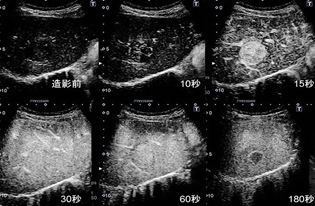

検査用のゼリーを塗りプローブ(探触子)を当てて観察します。

高周波数の音波を腹部にあて、臓器の状態を調べる検査です。心臓や肝臓、胆嚢、膵臓、腎臓、脾臓、乳腺の様子を観察することができます。検査は、X線検査でないので、「被ばく」もなく安全な検査です。

造影検査等の最新技術を用いた精密検査も積極的に行っています。